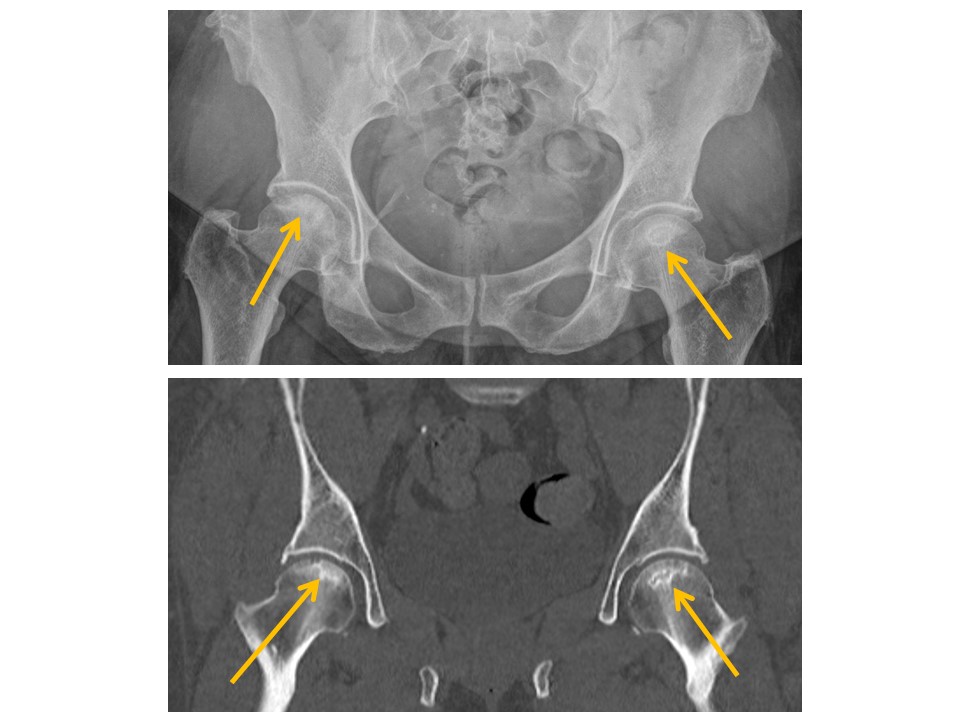

HIPS/PROXIMAL FEMURS

Hip alignment is abnormal. [Yes/No]

Femoral head fractures are present. [Yes/No]

There are fractures of the femoral neck, intertrochanteric region, or subtrochanteric region. [Yes/No]

There are avulsion fractures of the greater or lesser trochanters. [Yes/No]